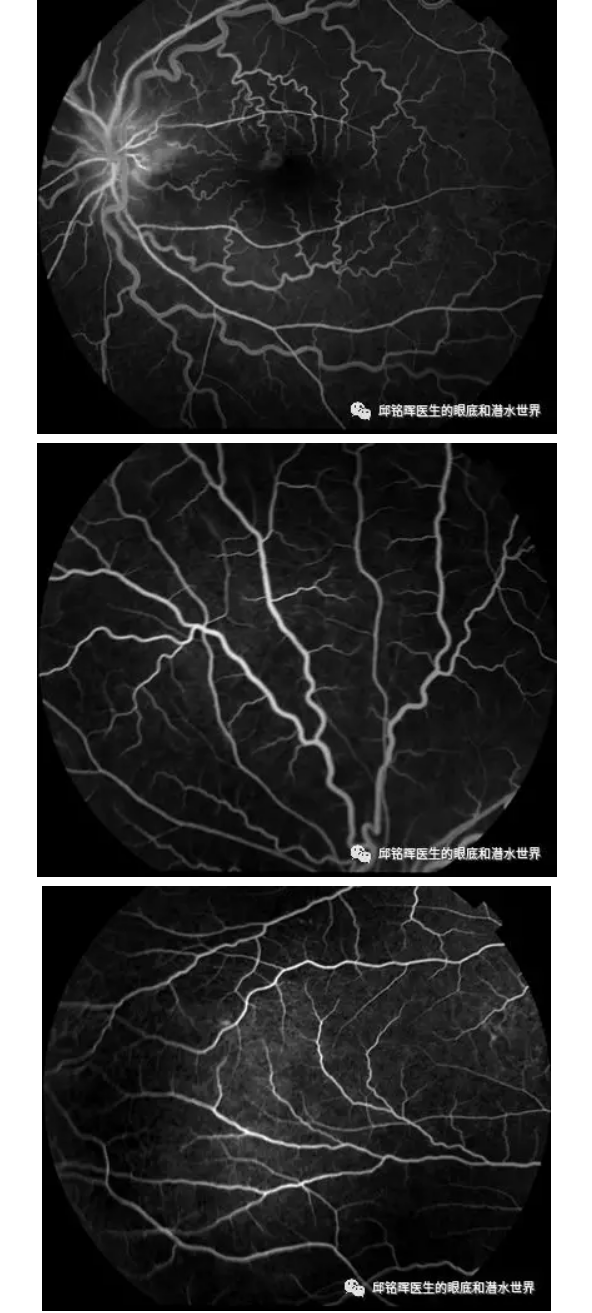

不同寻常的视网膜中央动脉阻塞